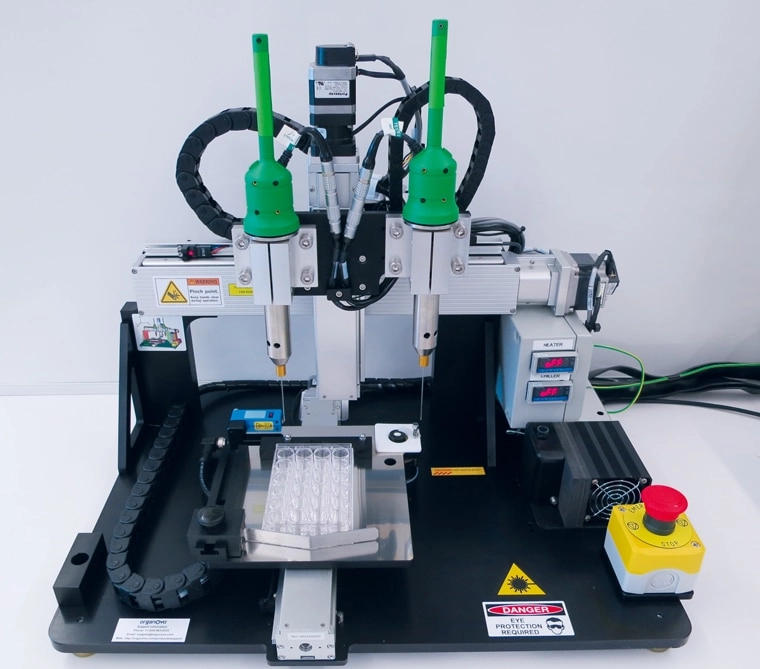

Специалист работает с российским биопринтером FABION 2 в лаборатории / © 3D Bioprinting Solutions Социальная реклама. ЧУ «Центр коммуникаций», ИНН 9705152344, erid 2VtzqvZpfv9.

Высокоточный 3D-биопринтер для создания живых тканей и органов / © Научный дивизион «Росатома»

До середины 2010-х биофабрикацию пытались вести на основе отдельных клеток, распыляемых гидрогелем. Плотность клеток в гидрогеле была низка, поэтому выращивание из нее тканей шло медленнее. В 2014 году российская компания 3D Bioprinting Solutions создала экструзионный биопринтер Fabion. Он впервые распылял предварительно выращенные сфероиды, что резко ускорило процесс получения целевой ткани.

Научно-образовательная лаборатория тканевой инженерии и регенеративной медицины НИТУ МИСИС, компактный биопринтер FABION / © МИСИС